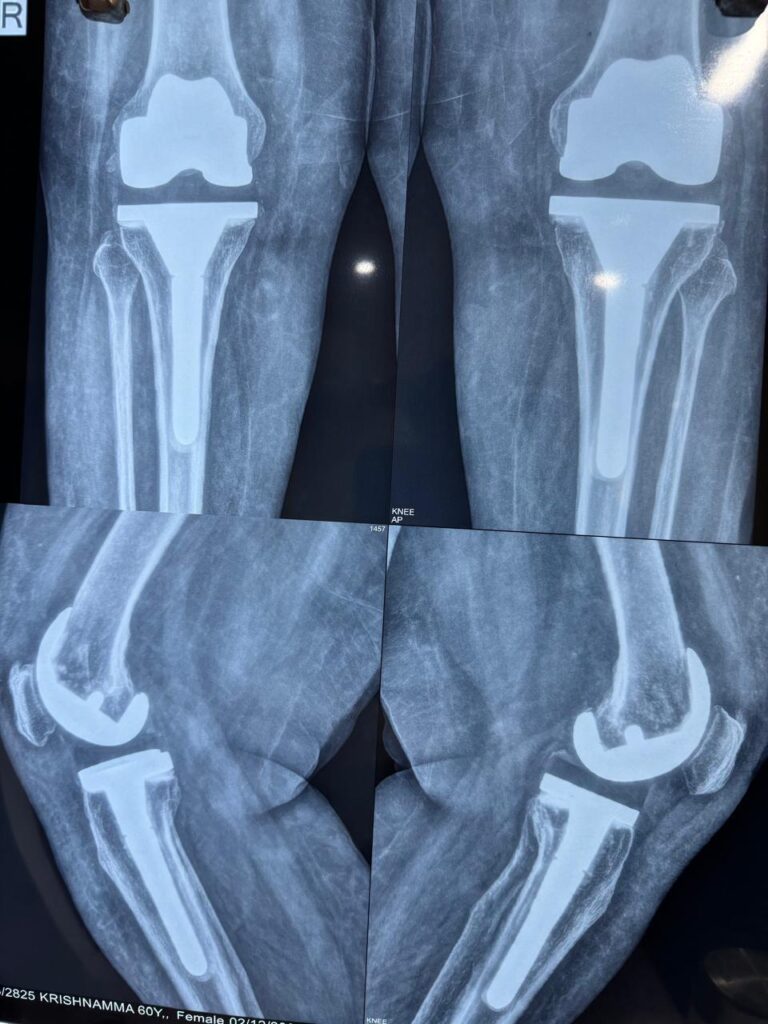

The surgeries were successfully performed, and Smt. Krishnamma’s recovery was closely monitored. Through expert surgical care and a structured physiotherapy regimen, she gradually regained strength and mobility.

Today, Smt. Krishnamma is a testament to the transformative power of modern medical care. She is now walking comfortably, free from the crippling pain that once dominated her life. Her happiness and satisfaction with the outcome of the surgery are evident in her newfound enthusiasm for life.